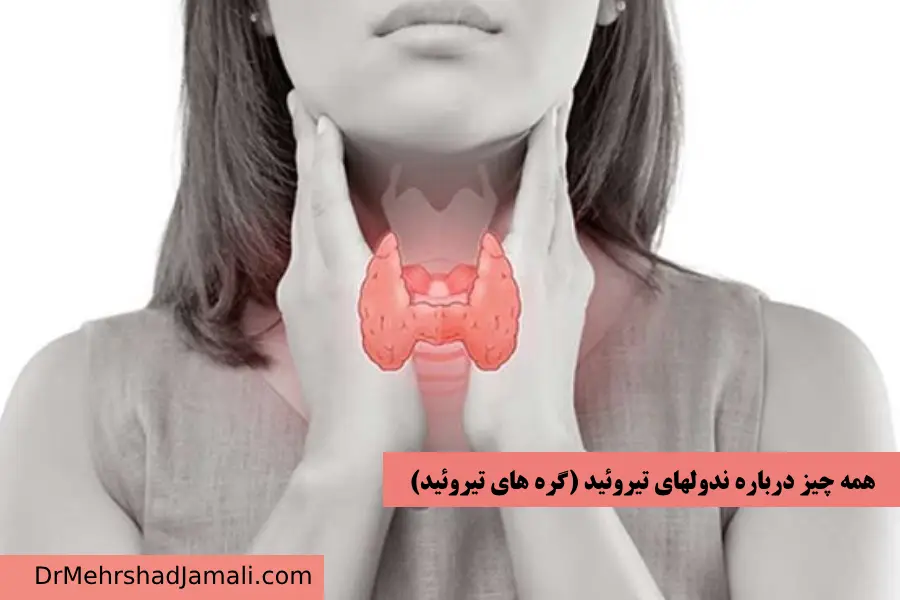

ندول تیروئید (گره های تیروئید)

در آموزش های گذشته در تفسیر سونوگرافی تیروئید با ندولهای تیروئید آشنا شدیم، که اگر کلمه غیرطبیعی را در نتایج تصوی

سونوگرافی تیروئید یا پاراتیروئید- تفسیر سونوگرافی تیروئید

تیروئید چیست؟ تيروئيد يك غده كوچك بال پروانهاي شكل است كه در شکل زیر قابل مشاهد